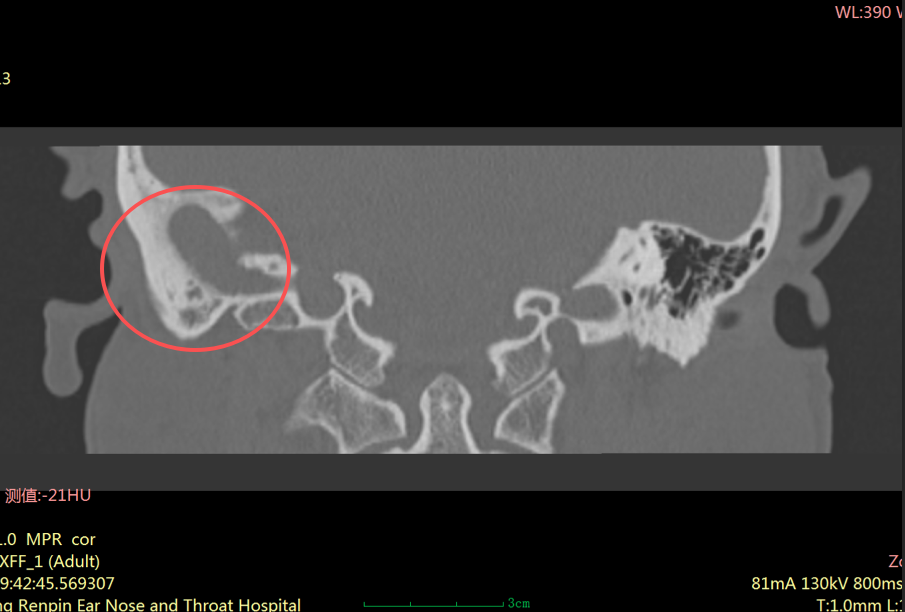

“患者右耳中耳腔已形成胆脂瘤,它像一颗不断侵蚀听骨的‘定时炸弹’,若再拖延,可能引发面瘫、颅内感染等严重并发症。”耳科主任张朝梅指着CT影像解释道。

胆脂瘤并非真正的肿瘤,而是中耳、乳突内形成的角化鳞状上皮堆积物。

虽然它不是肿瘤,但危害却不容小觑。它会像“寄生虫”一样,不断破坏周围的骨质,可能侵犯中耳的听小骨、面神经管、半规管等重要结构,进而导致

听力下降、耳鸣、面瘫,严重时甚至可能引发颅内感染,危及生命。